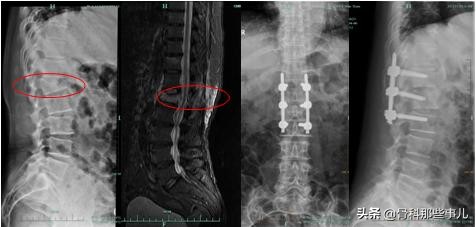

对于第③中情况,做这种微创的手术可能就不够了,需要常规做手术切口,医生要把骨折的地方压住神经的碎骨复位,或者干脆取掉,解除神经的压迫才能有好的手术效果,通常手术后需要使用钉子固定受伤的腰椎。好在对于老年人来说,这种情况并不多见。

椎体骨折,骨折块向后错位造成神经压迫;核磁共振看到水肿带一直延伸到后柱,微创手术不合适